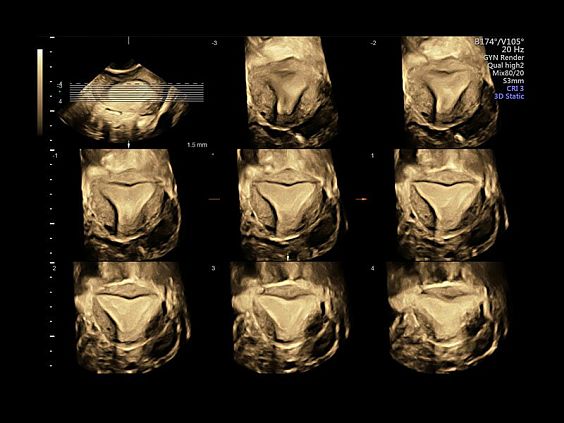

Клинические изображения

- Режим 3D.

- Режим 4D Realtime.

- SonoRenderlive – автоматическое определение границ конечностей и лица плода и получение объемного изображения в 3D/4D.

- Advanced 3D/4D - расширенный программный пакет 3D/4D:

- Опция 3D/4D Activation (режим 3D/4D, SonoRenderlive – автоматическое определение границ конечностей и лица плода).

- Томографический ультразвук (TUI).

- Уверенность в диагнозе благодаря превосходному качеству 2D- и 3D-изображений.

- Исключительный анатомический реализм благодаря технологии HDlive при исследованиях в 3D- и 4D-режимах.